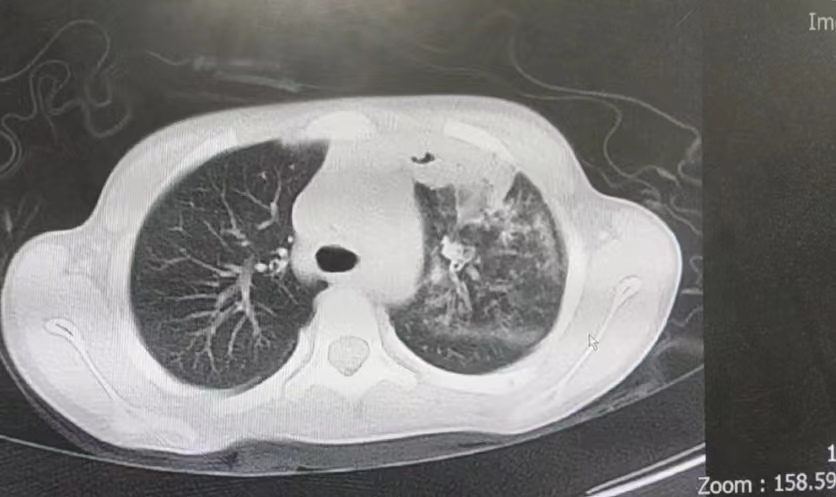

以上原因均造成今年肺炎发病率的升高,并且今年儿童肺炎支原体性肺炎不仅发病率增高,CT表现也重,多表现为双肺多发斑片样密度增高影或肺实变。